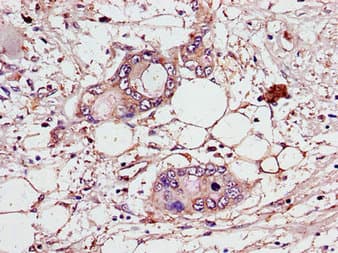

Rabbit Polyclonal CEP70 antibody. Suitable for WB, IHC-P, ICC/IF and reacts with Human, Mouse samples. Immunogen corresponding to Recombinant Fragment Protein within Human CEP70 aa 50-300.

Applications ICC/IF, IHC-P, WB